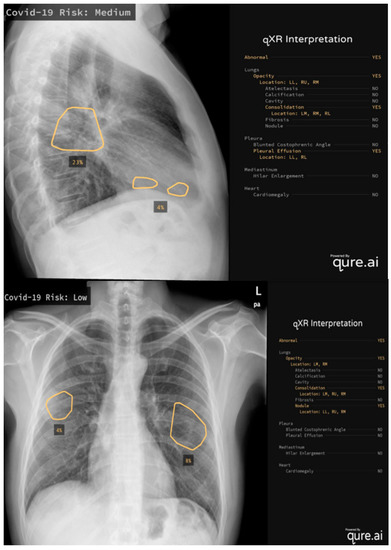

5. COVID-19